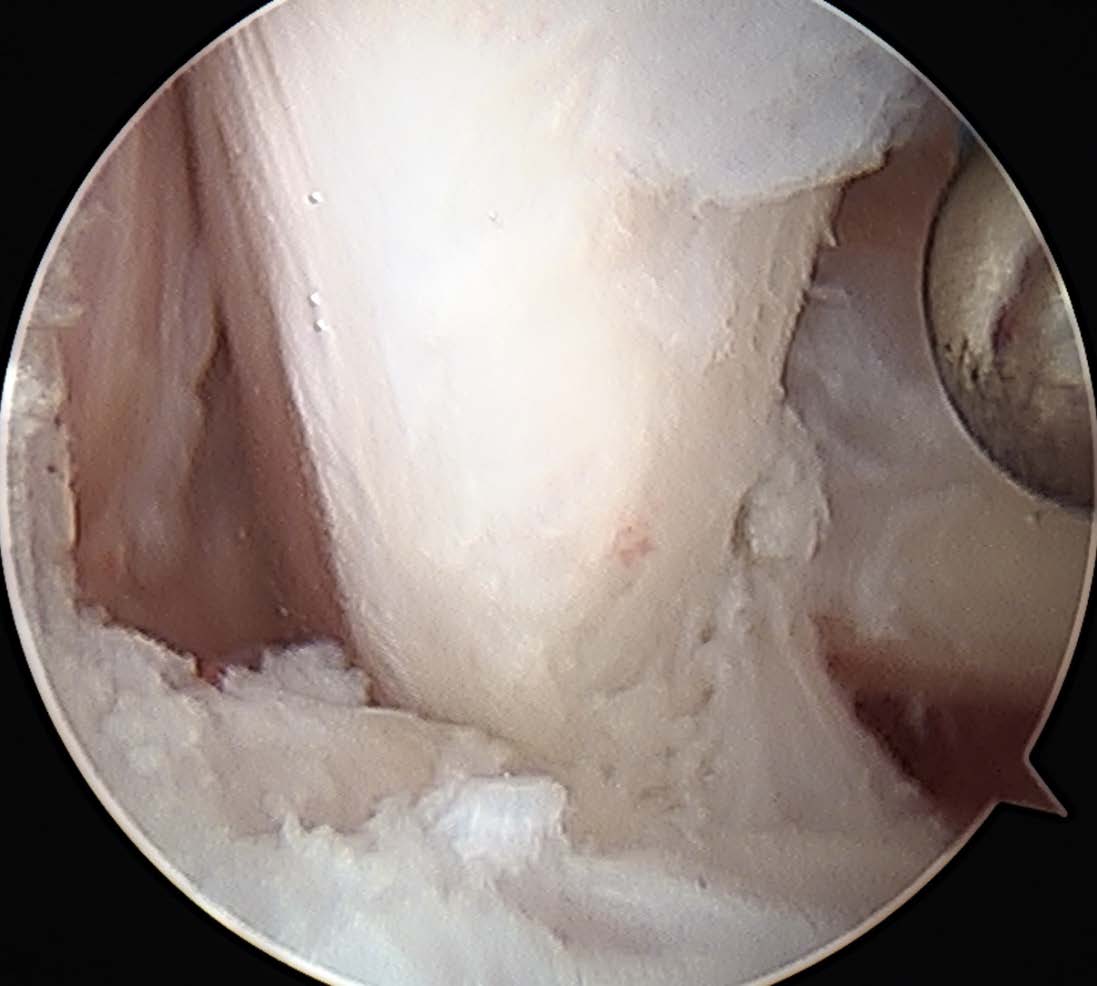

Posterior ankle impingement in athletes is often related to a previous sprain.7,11,12,15,16 Many times, soldiers who sustained syndesmosis injuries can develop a combination of soft tissue impingement lesions not only anteriorly but posteriorly as well (see first photo set above). We also see clicking, popping and snapping of the posterior tibiofibular ligament and posterior talofibular ligament in these cases. In a sense, we can see a posterior pseudo-version of Bassett’s ligament although this is not named as such. Whether this is a fraying of the ligament which now impinges on the posterior tibial lip or a true accessory ligament is not well-defined. Regardless, the imaging is often clear on MRI and intra-operatively (see second image set above). Almost every author states that symptoms always or only occur with plantarflexion, but I tend to see far more soldiers and athletes complaining of pain with dorsiflexion. To me, pain with stretching of the posterior capsule and distraction of the offending tissue makes far more sense that hurting with only plantarflexion.

Surgeons may utilize a multitude of scope sizes from 2.7 to 4.0 mm.4 Whether it is a zero, 30 or 70 degree apparatus depends on your comfort level. Goals are very simple once you are in the joint. Just like we do for the anterior ankle, we need to identify our landmarks and work systematically from one side to the next. I tend to utilize the posterolateral portal for the camera first prior to proceeding medially. I prefer to use a spinal needle and attempt to put the needle on the lateral side of the flexor hallucis longus tendon. I figure as long as I stay lateral to this tendon, I cannot hurt anything medially like the neurovascular bundle (see third photo above).